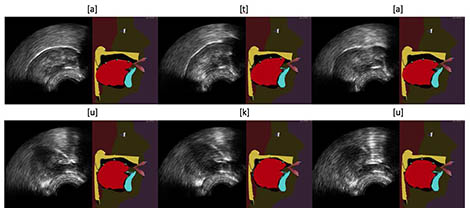

Example of tongue model animations of the GIPSA-Lab articulatory talking head from ultrasound images, using the Integrated Cascaded Gaussian Mixture Regression algorithm for [ata] (top) and [uku] (bottom) sequences.

For several years, researchers have been using ultrasound to design biofeedback systems. The image of the tongue is obtained by placing under the jaw a probe similar to that used conventionally to look at a heart or fetus. This image is sometimes deemed to be difficult for a patient to use because it is not very good quality and does not provide any information on the location of the palate and teeth. In this new work, the present team of researchers propose to improve this visual feedback by automatically animating an articulatory talking head in real time from ultrasound images. This virtual clone of a real speaker, in development for many years at the GIPSA-Lab, produces a contextualized — and therefore more natural — visualization of articulatory movements.